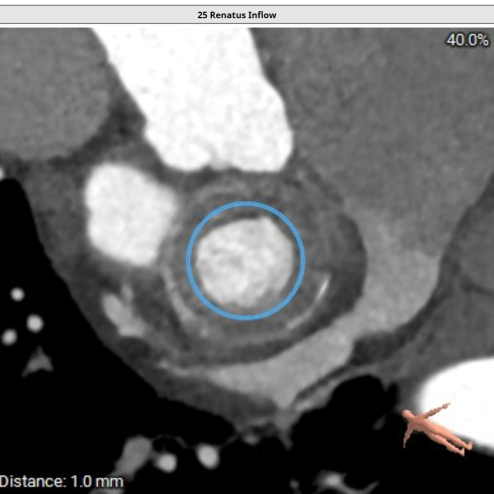

二尖瓣生物瓣架内径23mm,外径25mm,根据瓣架形态,符合25#Mosaic瓣膜

模拟23#Renatus植入

模拟25#Renatus植入